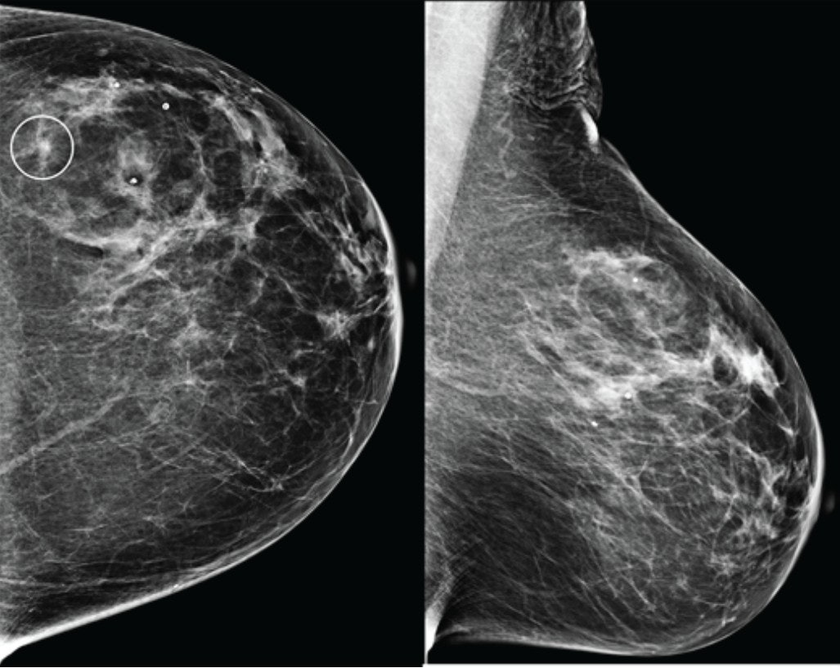

В конце августа 2025 года американский стартап Calidar представил инновационную систему 4D-маммографии, которая выводит точность диагностики злокачественных образований молочной железы на новый уровень. Эта платформа визуализации использует рентгеновскую дифракцию и искусственный интеллект для проведения исследования на молекулярном уровне.

Первая в своем роде система 4D-маммографии, разработанная компанией Calidar, позволяет решить существующие проблемы. Устройство измеряет, как рентгеновские лучи рассеиваются на молекулярном уровне: данный процесс известен как рентгеновская дифракция. Это создает уникальную структурную сигнатуру, которая отражает внутренний состав ткани молочной железы.«Диасофт» и «Центр «РИС» подтвердили безопасность решения Digital Q.ERP 12.4 т

В отличие от традиционных рентгеновских снимков, которые основаны на форме и плотности, рентгеновская дифракция предоставляет дополнительную диагностическую информацию о том, из чего состоит ткань. Эти специфичные данные позволяют классифицировать раковые и доброкачественные образования с точностью, в четыре раза превышающей показатели традиционных систем визуализации.[1]